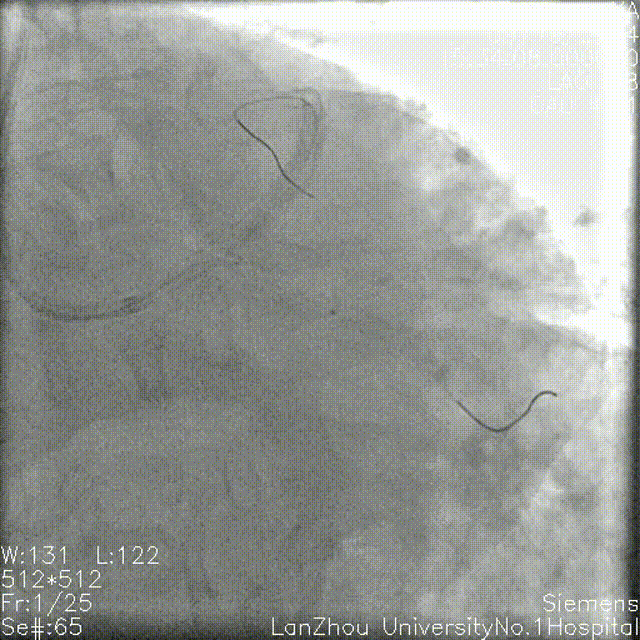

蜘蛛位造影:

左主干开口、体部未见明显狭窄;

第一对角支开口重度狭窄;

回旋支次全闭,开口、近端、中段重度狭窄,可见环形钙化。

右冠造影:

全程斑块伴有钙化;

第二弯可见支架影,支架未见明显再狭窄。